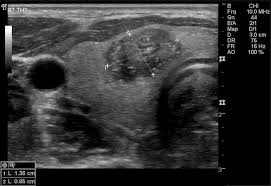

- ULTRASONIDO DE TIROIDES:

- El ultrasonido de tiroides es una herramienta fundamental en la evaluación de nódulos de tiroides.

- Utiliza ondas de sonido de alta frecuencia para obtener una imagen de la tiroides.

- Esta prueba es muy precisa y fácilmente permite determinar si un nódulo es sólido o si está lleno de líquido (cístico), y además permite medir con precisión el tamaño del nódulo.

- El ultrasonido también permite identificar nódulos sospechosos ya que algunas características del ultrasonido son más frecuentes en nódulos con cáncer de tiroides que en nódulos que no son cáncer.

- El ultrasonido de tiroides también permite identificar nódulos que son muy pequeños para detectar en el examen físico. El ultrasonido también se usa para guiar la aguja directamente al nódulo cuando su doctor piensa que una biopsia es necesaria.

- Luego de completar la evaluación inicial, el ultrasonido de tiroides puede usarse para seguir de cerca a los nódulos de tiroides que no requieren cirugía para determinar si estos están creciendo o haciéndose más pequeños con el paso del tiempo.

- El ultrasonido es una prueba no dolorosa que muchos doctores pueden hacer en su oficina.